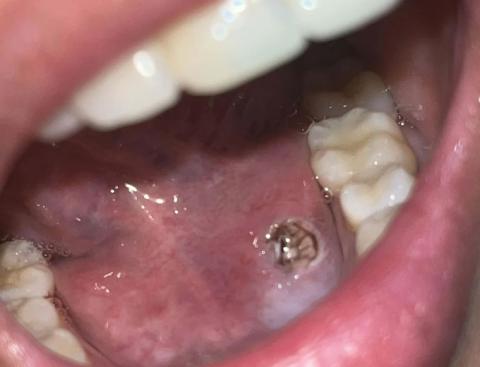

Swollen Tongue Case Analysis and Healing Timeline

Teeth Case – Full Analysis and Provisional Diagnosis (Zoom 100%)

This assessment is based on a single photographic image. A definitive diagnosis requires an in-person oral examination. Tongue swelling can have multiple causes; persistent or worsening symptoms require prompt professional evaluation.

1. Visual Findings (Deep Examination)

Tongue (dorsal surface):

Noticeable generalized swelling with a rounded, enlarged appearance.